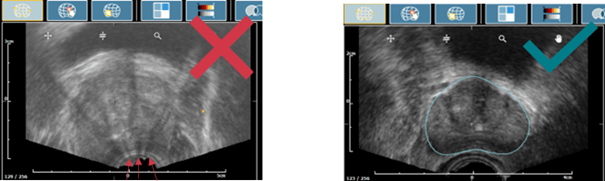

b. Prostate incomplète

- Assurez-vous que l’ensemble de la prostate soit inclus dans le Panorama.

- Qu’il y ait suffisamment de gel sur la tête de sonde

- Qu’il n’y ait pas de bulles d’air dans le protection de la sonde